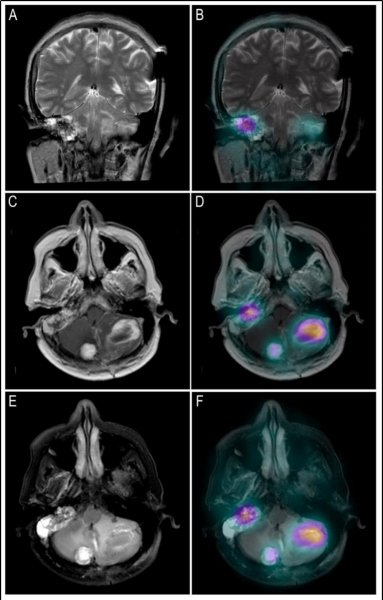

En las imágenes planares se observan múltiples áreas de captación anormal en la fosa posterior y en el aspecto lateral del hilio renal derecho (fig. 1). Se identifican tres lesiones cerebelosas con componente sólido realzante y quístico, altamente vascularizadas, que presentan aumento de perfusión y generan edema extenso obliterando el cuarto ventrículo, consistentes con hemangioblastomas (fig. 2). Existe otra lesión que genera invasión ósea de la mastoides con compromiso del oído interno; en la RM es isointensa e hiperintensa en las secuencias T1, hiperintensa en las secuencias T2, con captación del medio de contraste, por tumor del saco endolinfático (fig. 2). En la valoración de la cavidad abdominal se detecta una lesión sólida en la cabeza/proceso uncinado del páncreas, hipodensa respecto al resto del parénquima, compatible con tumor neuroendocrino (fig. 3).